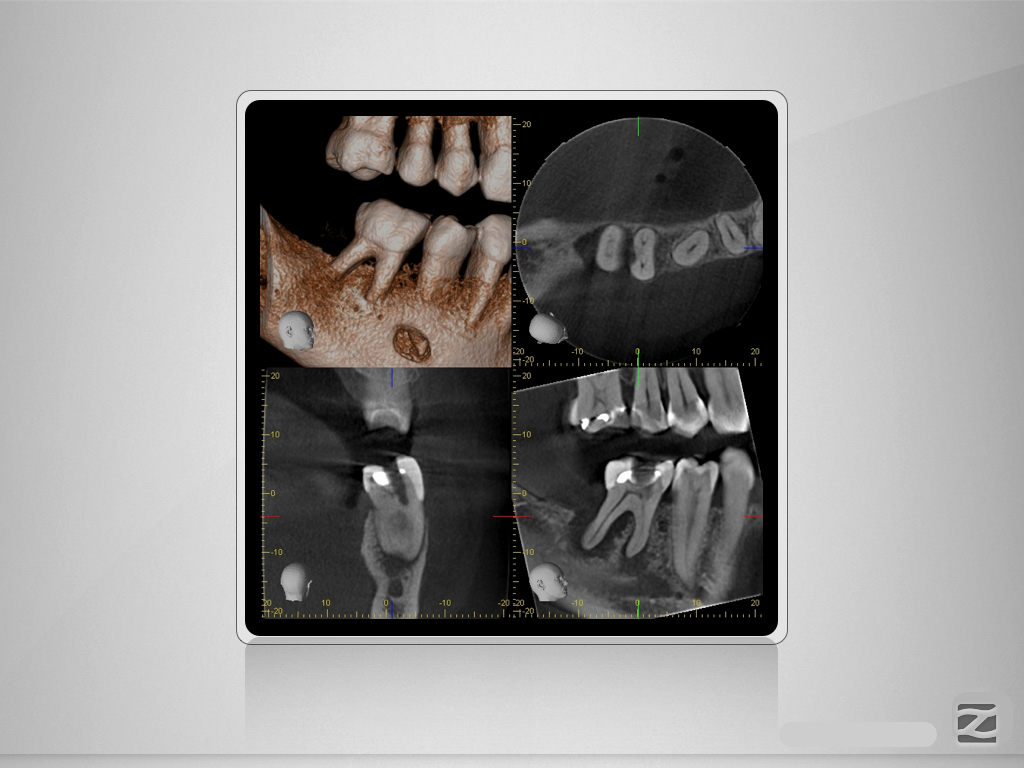

46D.004

Für oder Wider?